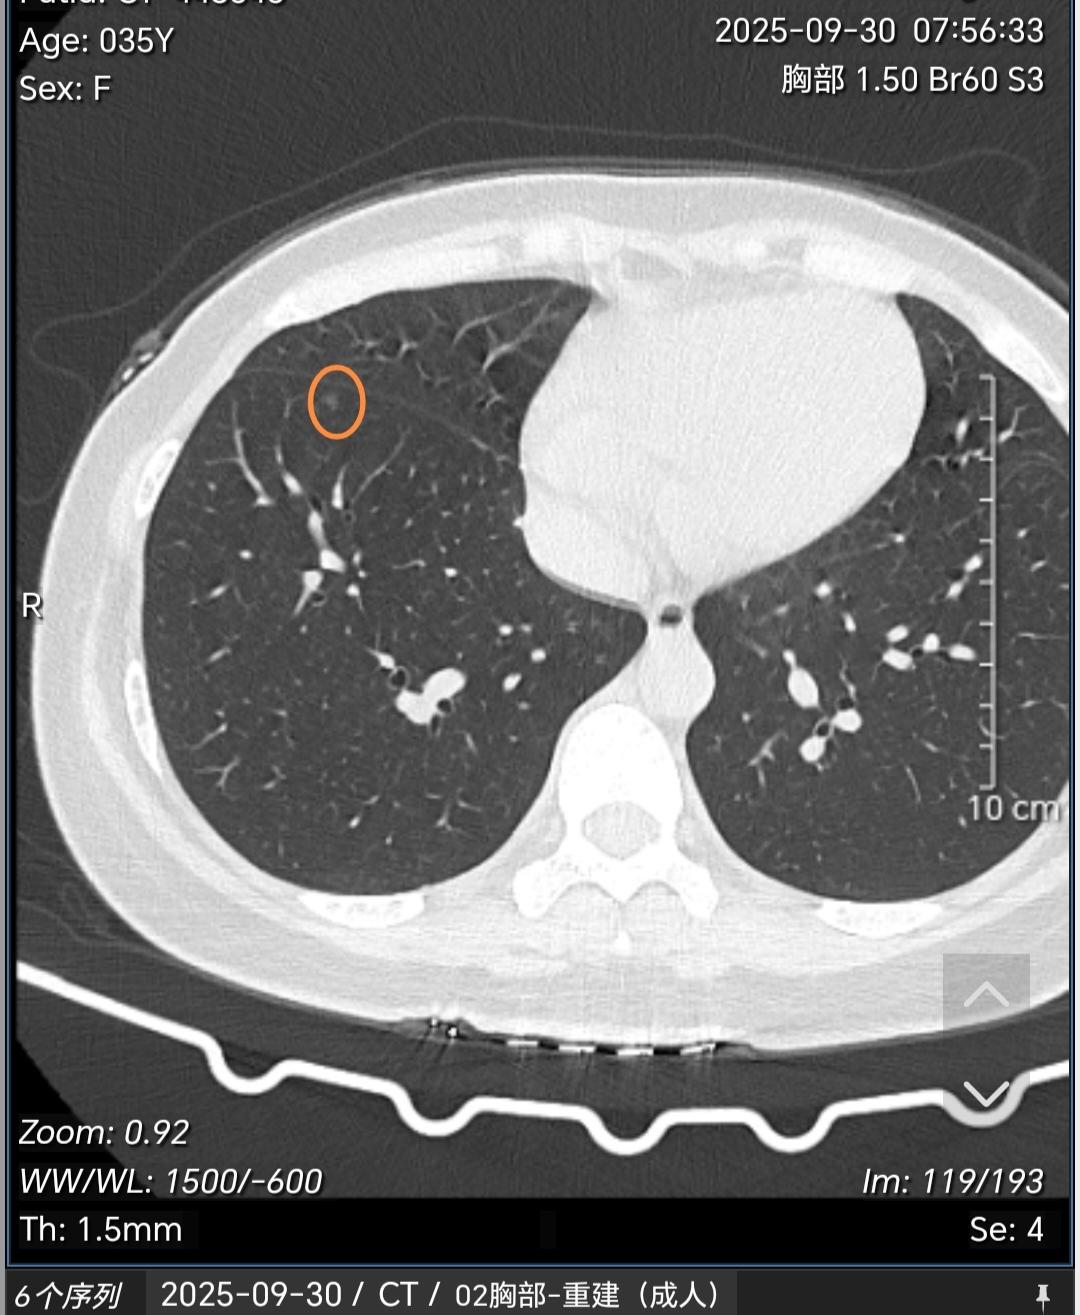

多发磨玻璃结节常见原因有哪些?如何处理?这种多发磨玻璃结节如果经半年左右观察没有明显缩小或消失一般多考虑是肿瘤性的,这类多发肿瘤性的磨玻璃结节最常见的原因就是遗传(基因易感体质),再者就是职业原因接触一些高致癌物质(苯、酚、氡、放射性物质、重金属等)。其他烟、空气污染等所致的肿瘤多见的是单发。那么对于这类结节怎么处理?对于这类多发的,一般手术很难切净,所以建议先观察,后续发现哪个结节有增大再以这个结节为主进行包括手术、消融或立体定向放疗在内的综合治疗策略。